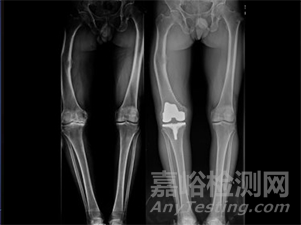

膝關(guān)節(jié)置換手術(shù)機(jī)器人

實(shí)現(xiàn)精微擺鋸,多角度截骨平面,快速精確的自動(dòng)定位,亞毫米級(jí)精度的安全高效截骨,斷電保護(hù)模式避免截骨超過規(guī)劃范圍,徹底擺脫全膝關(guān)節(jié)置換手術(shù)對(duì)截骨導(dǎo)板的依賴,相較于傳統(tǒng)手術(shù)具有更高的智能化程度。

圖源柳葉刀官網(wǎng)

2021年9月5日,杭州柳葉刀機(jī)器人有限公司全新研發(fā)的RobPath膝關(guān)節(jié)置換手術(shù)導(dǎo)航定位系統(tǒng)用于全膝關(guān)節(jié)置換手術(shù)的前瞻性、多中心、隨機(jī)、單盲、平行對(duì)照臨床試驗(yàn)的臨床研究者會(huì)議順利召開,這標(biāo)志著RobPath膝關(guān)節(jié)置換手術(shù)機(jī)器人中國注冊(cè)臨床試驗(yàn)的正式啟動(dòng)。